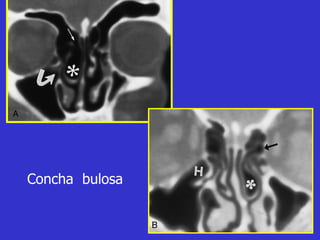

Este documento describe las diferentes proyecciones radiográficas utilizadas para examinar los senos paranasales, incluyendo las proyecciones básicas de Caldwell, Waters lateral y las proyecciones especiales como Hirtz y Waters mentonasal. También describe las diferentes estructuras anatómicas que componen el complejo ostiomeatal anterior y posterior de los senos paranasales.